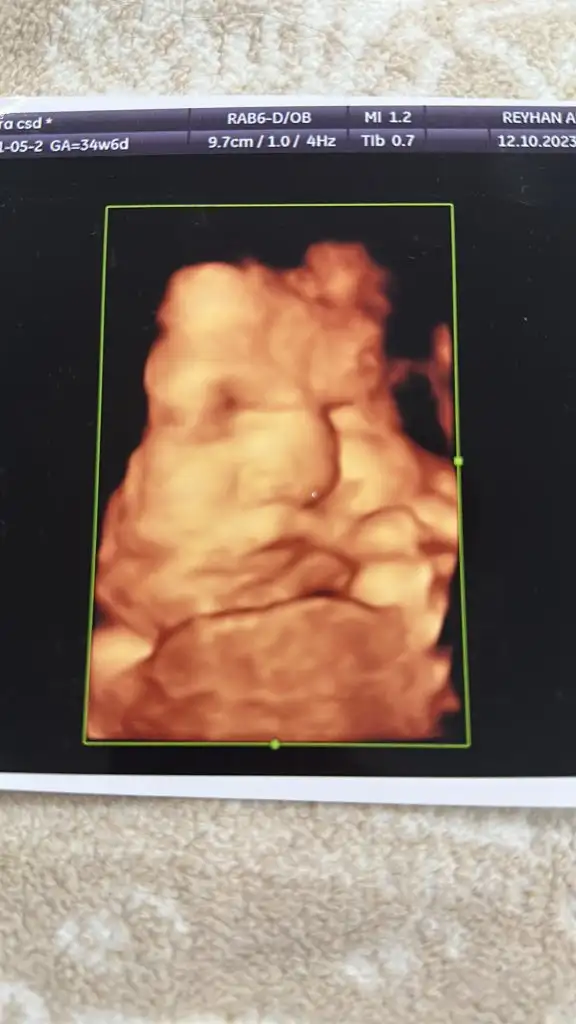

Offf burdan bile belli yanakson yaısırcan o yanakları yiycen böle üzerine tuz serpcen, biraz limon sıkcan cok tatlı ya dengelesin, hapur hupur yiycen

Ya çok tatlı tontişşKızlar hepinizin mesajını okuyamadım mazur görün çok fazla da mesaj birikmiş. 2 yaşında bebeğimde var ancak toparlanabildim. Şehir hastanesinde yatış vermişti doktor red imzaladım. Açlık şekerim iyi çıkmış yalnız hemoglobin A1C sınırfa çıkmış.Kolestaz için safra asidi bir kaç güne çıkacakmış. Gelişimi çok ilerde 3.500 olduğu nst de sancı çıktığı için doktor riske atmak istememiş. Doktor ani bebek ölümü riski oluşabilir ondan dolayı yatış verdim dedi biraz korkuttu kendi doktorumu aradım hemen muayeneye gittim. Gelişimi burda da 2-3 hafta ileri çıktı. 3.100 gram olmuş. Burda da kan ve nst sonucum çıktı şeker aynı sınır nst sancısıx çıktı doktor haftaya tekrar kontrole çağırdı endokrine ve diyetisyene sevk etti. Yatış vermedi. Kolestaz içinde sonuç bekliyoruz ama her şey yolunda giderse 38-39 da doğuma alırım dedi. Sadece bizim kız biraz şişko